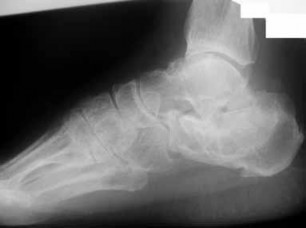

ORTHOPEDIC MCQS ONLINE 015FOOT and Ankle CLINICAL SITUATION FOR QUESTIONS 1 THROUGH 4 A B Figures 1a and 1b a…